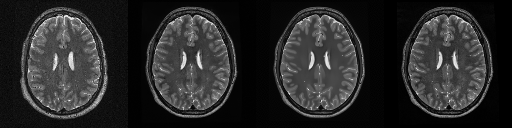

HCP T2w dataset

We utilize images from the publicly available Human Connectome Project (HCP) [51] T2-weighted (T2w) images dataset for the task of compressed sensing, which contains brain images from 47 patients. The HCP dataset includes cross-sectional images of the brain taken at different levels and angles.

Compressed sensing

We train a flow-based model from scratch on 10,000 randomly sampled images, utilizing the ncsnpp architecture [9] with minor adaptations for grayscale images. We employ compression rates , meaning . The measurement operator is given by a subsampled Fourier matrix, whose sign patterns are randomly selected. We evaluate our reconstruction algorithm’s performance on 200 randomly sampled test images.

We present the quantitative and qualitative results of compressed sensing in Tab. 1 and Fig. 4, respectively. As shown in Tab. 1, our method consistently achieves the best performance across varying compression rates . In Fig. 4, our method produces reconstructions that are more faithful to the original images, with fewer artifacts, leading to higher accuracy and clearer details.